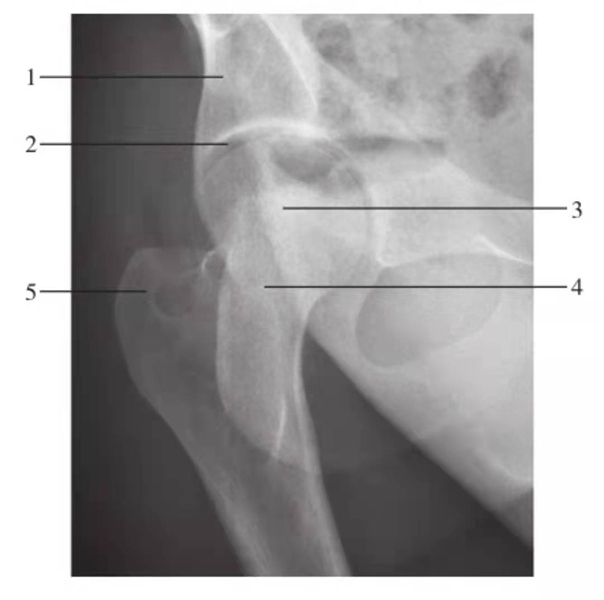

髋关节后前斜位

图5 髋关节后前斜位(谢氏位)

1.髂骨;2.关节间隙;3.股骨头;4.股骨颈;5.大转子